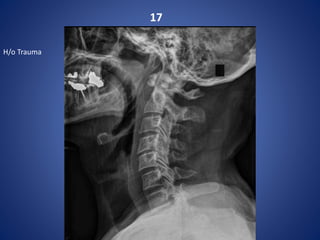

17

H/o Trauma

Extension teardrop fracture